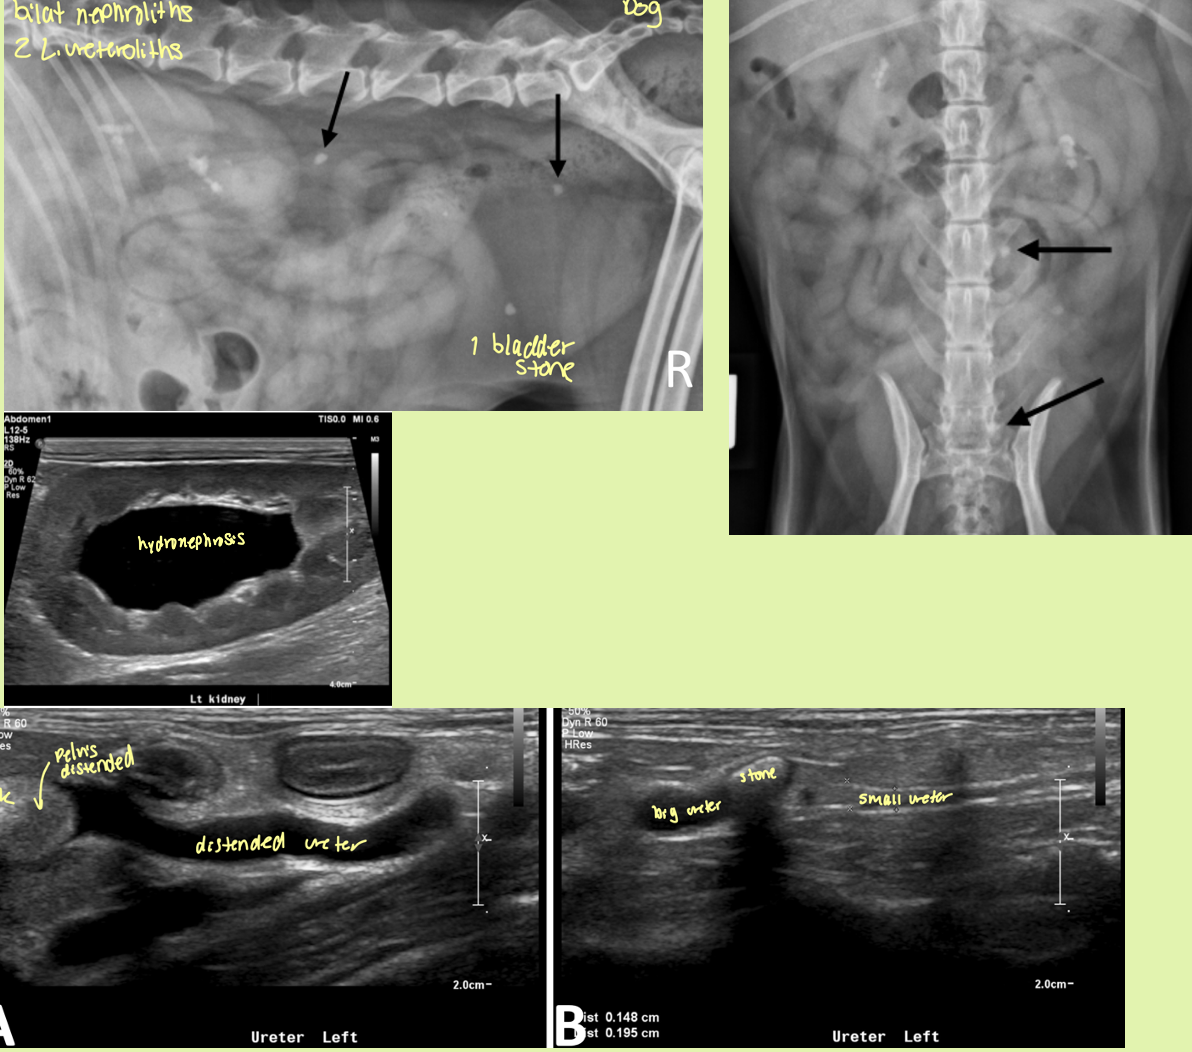

hydronephrosis is caused by

partial or complete obstruction of urine outflow in renal collecting system or ureters

enlarged smooth kidneys with distended pelvis ± distended ureters

hydronephrosis

rad and ultrasound findings of ureteroliths

Rad findings - Can be seen

Ultrasound findings

hyperechoic structures with distal acoustic shadowing

Variable size

If obstruction—> hydronephrosis and hydroureter prox. and a normal ureter distally

degree of distension of renal pelvis and ureter depend on what 2 factors

degree of severity

chronicity of obstruction